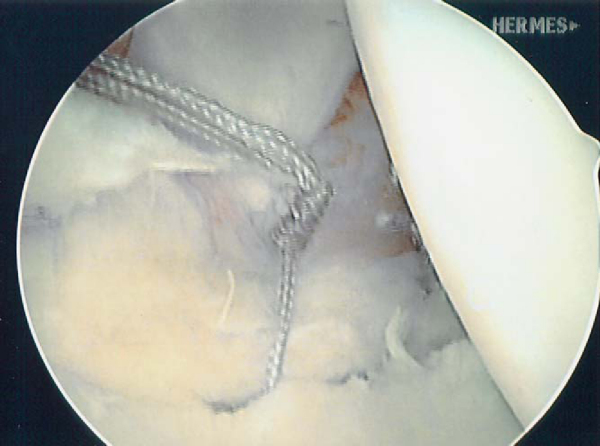

| • | The completed multi-pleated capsular plication reduces volume and improves stability ( Fig. 9-10 ). |

|

Figure 9-10 (From Sekiya JK. Arthroscopic labral repair and capsular shift of the glenohumeral joint: technical pearls for a multi-pleated plication through a single working portal. Arthroscopy 2005;21:766.) |